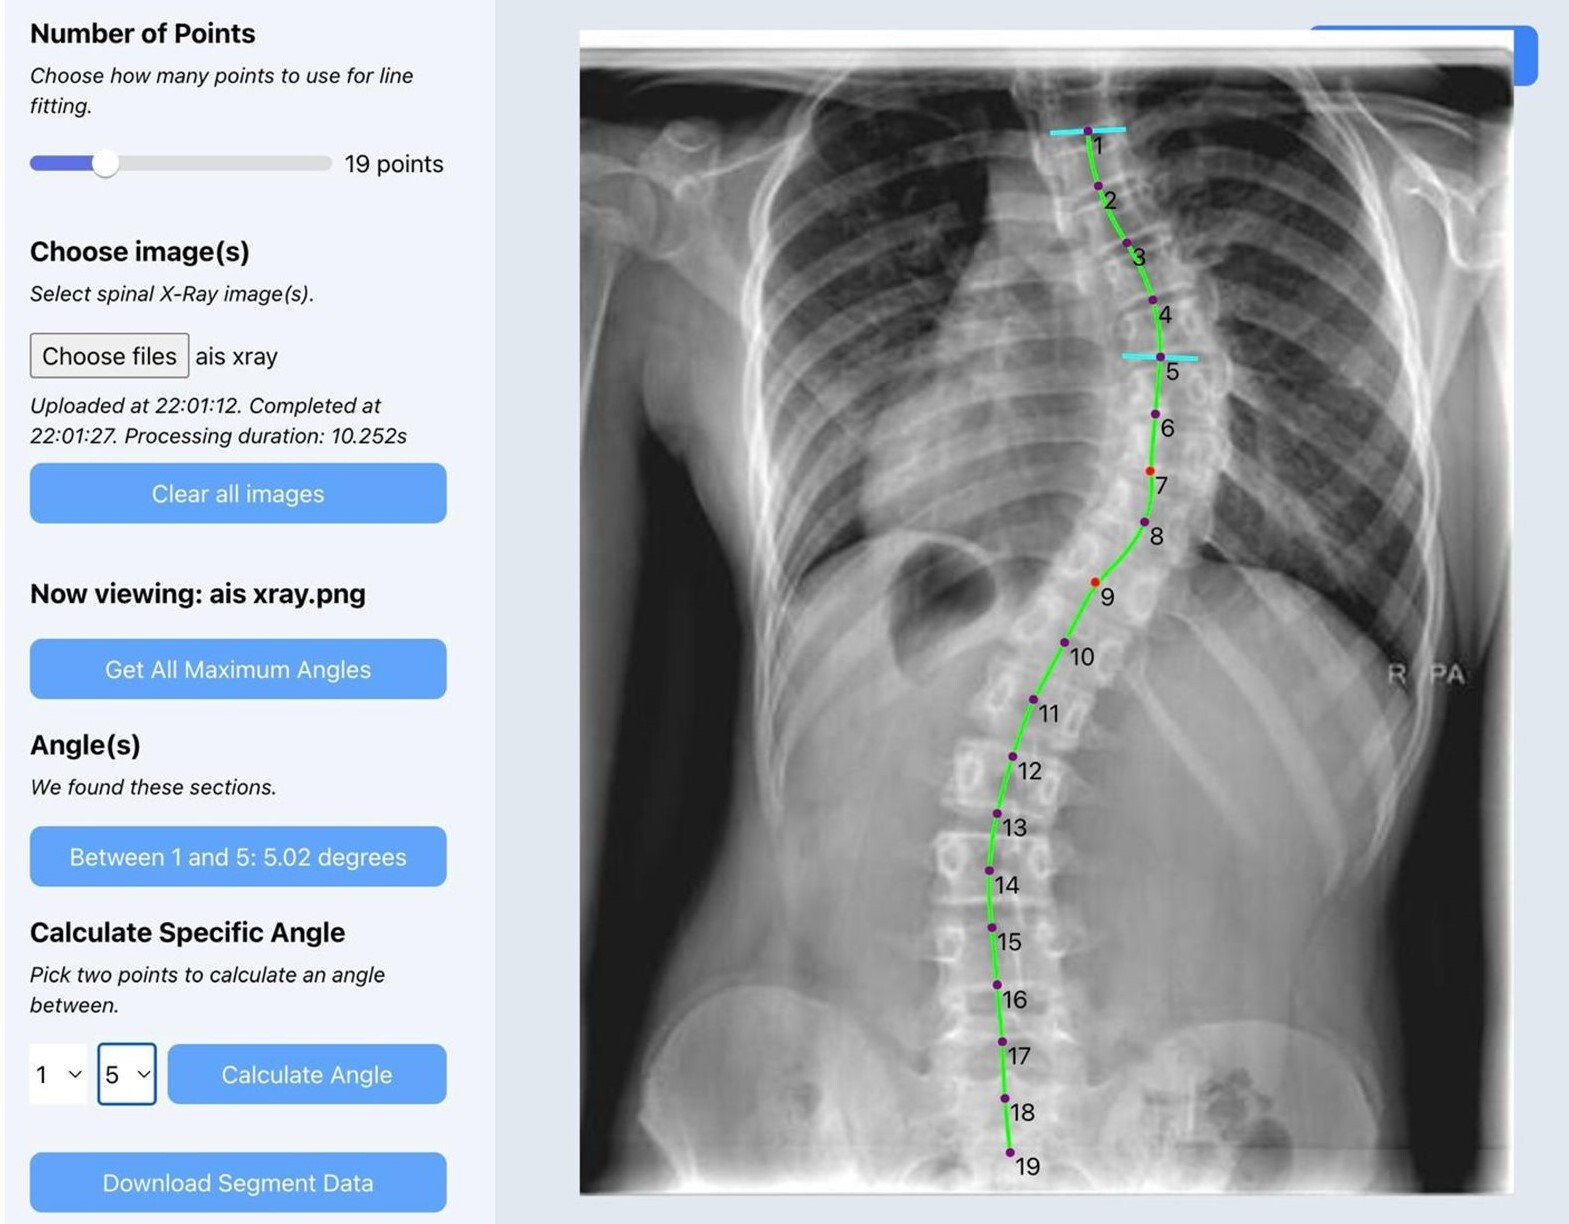

After uploading a radiograph, the software performs spinal segmentation, identifies vertebral endplates, and calculates the Cobb angle(s). For patients with more than one spinal curve, the software detects and displays the largest angles automatically. Users are given the option to refine the measurement manually or choose among alternate curves. Once finalized, users can export the radiograph with annotated angles as a PNG file, and all measurement data can be saved for further analysis. No patients were involved in the design or conduct of this study.

Figure 2 demonstrates the software user interface accurately measuring Cobb angles on a plain coronal scoliosis radiograph.